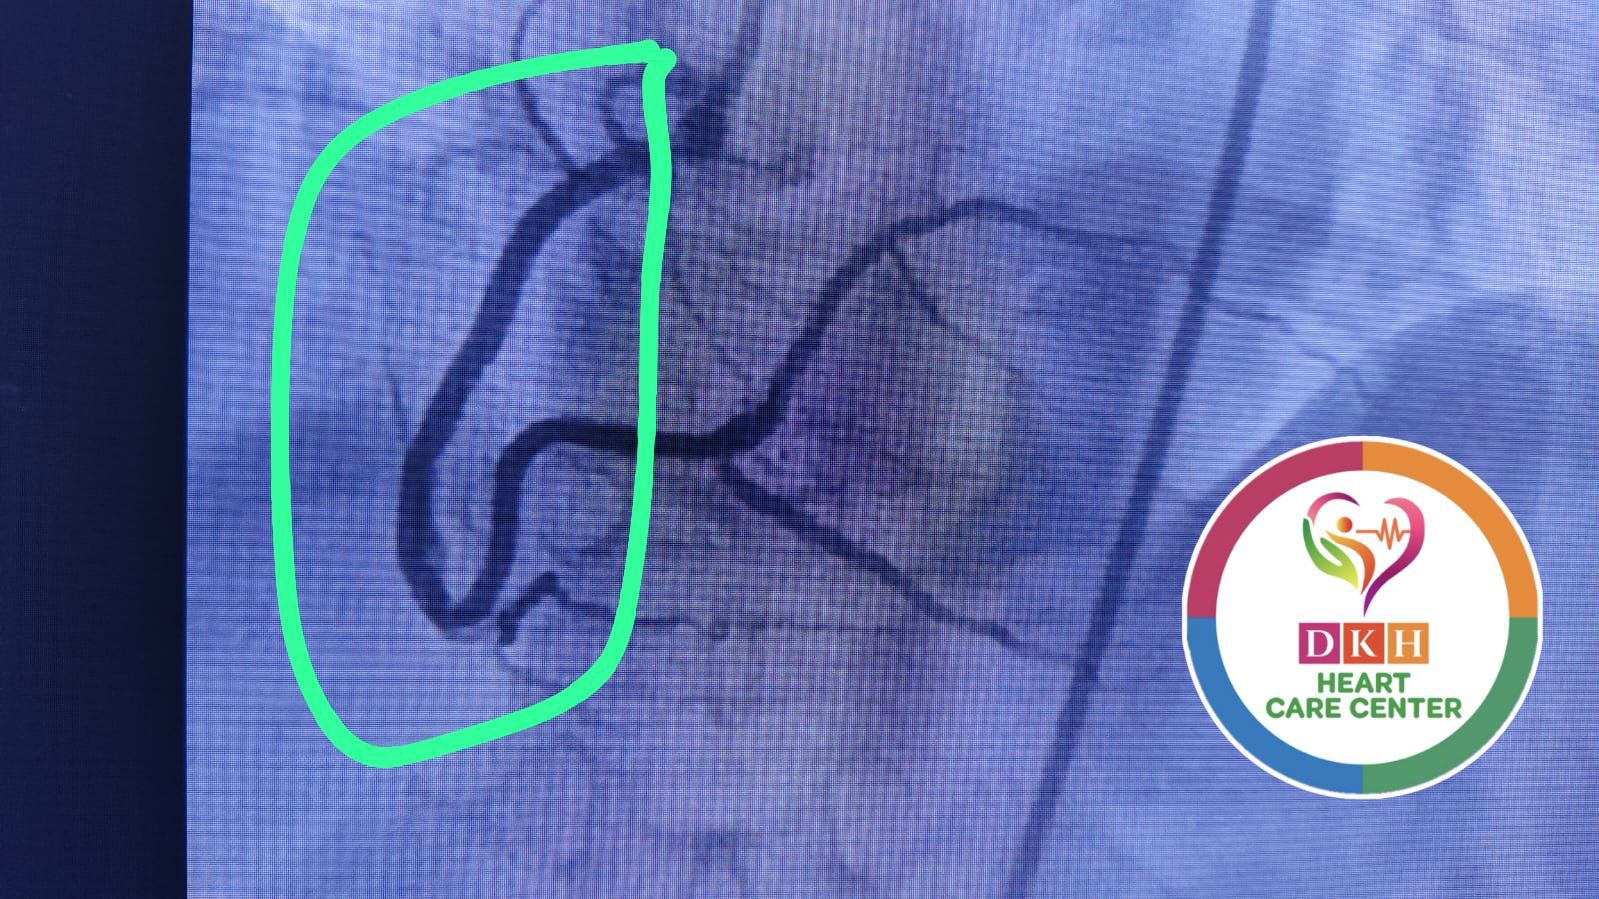

Deepa Kannan Hospital Heart Care Center & Cath Lab stands as a beacon of excellence in cardiovascular medicine. With state-of-the-art catheterization laboratory facilities and a team of renowned cardiac specialists, we are committed to providing comprehensive heart care services that combine cutting-edge technology with personalized patient care.

State-of-the-art cardiac catheterization laboratory with advanced imaging technology